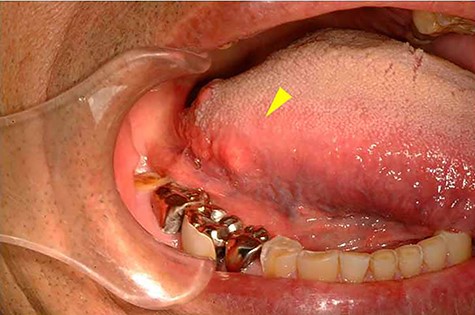

A 63-year-old man was referred to our hospital for treatment of a nodule on his tongue in May 2003. His medical history included Wolff–Parkinson–White syndrome and atrial fibrillation, both of which were controlled adequately by his primary care physician. Physical examination revealed very slight swelling at the right edge of his tongue. The patient reported some spontaneous pain. It was diagnosed as inflammation of the foliate papilla; the patient was followed-up with a gargle prescription. In September 2005, an elastic soft mass, 4 mm in diameter, was observed along the right edge of his tongue (Fig. 1). It was clinically diagnosed as a benign tumour and removed under local anaesthesia. Microscopically, the lesion was composed of multiple cysts of various sizes and shapes, with or without papillary intraluminal short projections (Fig. 2). Many cyst cavities contained eosinophilic fluid. The lesion was well-delineated, but the capsular structure was ill-defined. The stroma was fibrous connective tissue without lymphocytic components. The cystic cavities were lined by a bilayered epithelium composed of luminal columnar cells and basal cuboidal cells. Both luminal and basal epithelial cells were eosinophilic; some clear cells were seen (Fig. 3). Mitotic figures and cellular atypia of epithelial cells were not seen. Immunohistochemically, both luminal and basal cells were CAM5.2+, basal cells were p63+, apical half of the luminal cells were 34βE12+, and the liminal surface was CEA+. The specimen was diagnosed as cystadenoma, based on the histopathological findings.

Intra-oral photograph showing the tumour of the tongue (arrowhead).